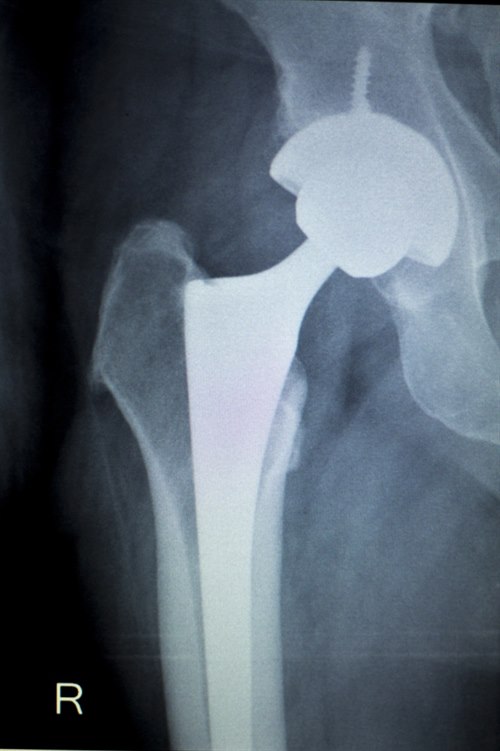

Total hofteprotese. Røntgenbilde: Colourbox.comVed brudd uten feilstilling er det enighet om at behandlingen skal være skruer eller nagler uansett alder. For brudd med feilstilling, derimot, anbefales ulike former for kirurgi basert på alder, bruddtype og andre forhold. For noen er det best å sette inn en halvprotese (bare leddhodet skiftes), men for andre er det bedre å sette inn en totalprotese (skifter både leddhode og leddskål).